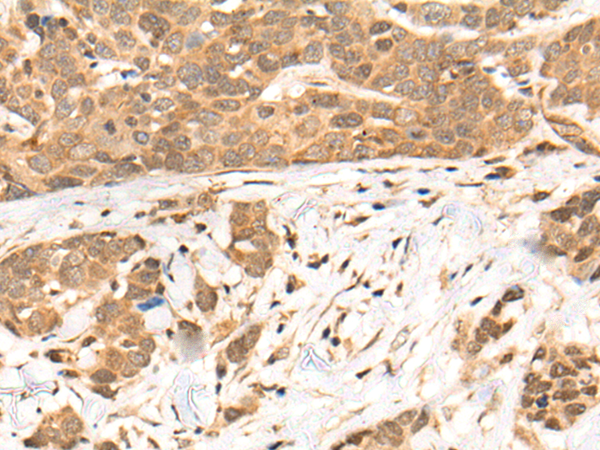

分类: 科研抗体货号: P02437别名: C4BP应用: IHC反应种属: Human